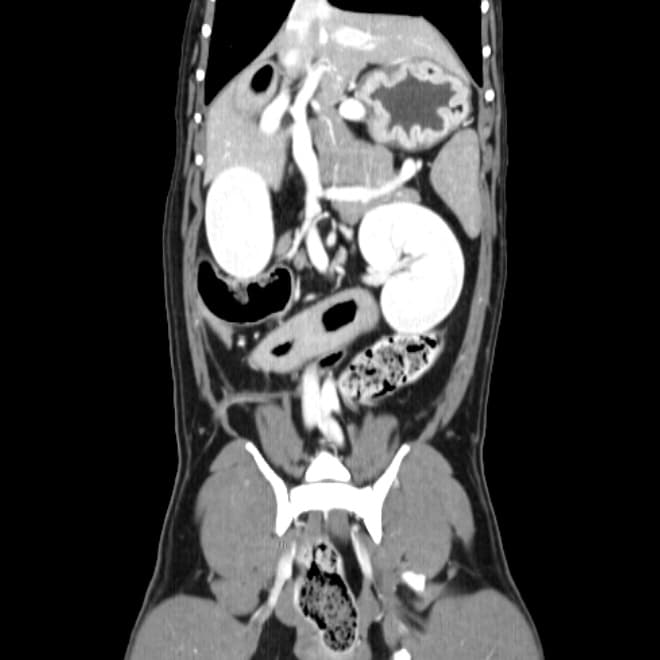

동탄 1 신도시 최초 Aquilion CX/128 slice CT를 동물병원에 도입하였습니다. 최고 사양 CT 모델 Aquilion CX/128 slice를 활용하여 0.5 mm의 얇은 128개의 단면 영상을 신속히 획득 할 수 있어 마취 시간을 단축시킬 수 있습니다. 또한, 128 슬라이스의 고화질의 CT 영상을 통해 영상 왜곡을 최소화하고 X-ray에서는 확인하기 힘든 5 mm 이하의 미세 병변도 확인이 가능하여 정확한 진단을 할 수 있습니다. 심화 진단이 필요한 경우, 조영제 인젝터를 통한 동맥기 촬영으로 종양 유래 확인, 간 질환 진단, 심혈관계 진단이 용이합니다. 저희 동탄시티동물의료센터에서는 본원 환자뿐 아니라 1차 동물 병원과의 CT 촬영 의뢰 시스템을 통해서 원활한 협진이 가능하도록 최선을 다하고 있습니다.

0164 채널 CT 촬영을 통해서 신속하게 고화질 영상을 얻어, 종양 유래 확인 및 전이 평가, 간문맥단락증(PSS), 선천적 뼈 기형과 같은 심화된 진단을 할 수 있습니다.

64채널 검출기 시스템 128

슬라이스 이미징 능력

고속 스캔 및 높은 해상도 제공

저선량 기술 적용으로 환자 방사선 노출 감소

흉복부, 골격계 전반의 선명하고 우수한 영상을 저선량으로 촬영이 가능